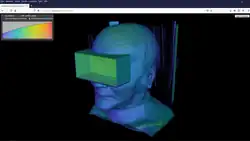

Studierfenster or StudierFenster (SF)[1][2][3] is a free, non-commercial open science client/server-based medical imaging processing online framework. It offers capabilities, like viewing medical data (computed tomography (CT), magnetic resonance imaging (MRI), etc.) in two- and three-dimensional space directly in the standard web browsers, like Google Chrome, Mozilla Firefox, Safari, and Microsoft Edge. Other functionalities are the calculation of medical metrics (dice score[4] and Hausdorff distance[5]), manual slice-by-slice outlining of structures in medical images (segmentation[6][7]), manual placing of (anatomical) landmarks in medical image data, viewing medical data in virtual reality, a facial reconstruction and registration of medical data for augmented reality,[8] one click showcases for COVID-19 and veterinary scans, and a Radiomics module.

VR viewer

The VR Viewer (or Medical VR Viewer) enables viewing (medical) data in Virtual Reality (VR) with devices like the Google Cardboard or the HTC Vive (via the WebVR App).[31] For viewing the data in VR, it needs to be converted to the VTI (.vti) format, which can be done with open-source, multi-platform data analysis and visualization application ParaView[32]